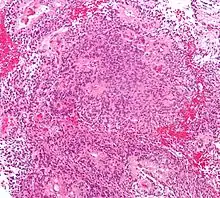

Патологическая анатомия

Эпендимомы головного мозга чаще располагаются внутри желудочковой системы, реже отмечается паравентрикулярная локализация этих опухолей. Эпендимомы спинного мозга растут интрамедуллярно (внутри спинного мозга), а развивающиеся из эпендимы терминального желудочка или терминальной нити — экстрамедуллярно (вне спинного мозга). Макроскопически опухоль имеет вид чётко отграниченного узла, в котором на разрезе могут определяться крупные гладкостенные кисты. В зоне исходного роста, как правило, отсутствуют чёткие границы с тканью мозга[2].

Согласно Международной гистологической классификации 1979 года выделяют четыре типа данных новообразований[2]:

- Основным гистологическим типом является истинная эпендимома , для которой типично наличие периваскулярных и истинных «розеток». Периваскулярные «розетки» («псевдорозетки», «лучистая корона») состоят из клеток новообразования, которые располагаются вокруг кровеносных сосудов. В истинных «розетках» опухолевые клетки находятся вокруг каналов, которые выстланы эпендимарными клетками.

Кроме данных гистологических типов также выделяют злокачественный вариант эпендимомы — анапластическую эпендимому или эпендимобластому. Для данного типа характерны гистологические признаки анаплазии. При этой форме отмечается метастазирование опухолевых клеток по ликворным путям[2].